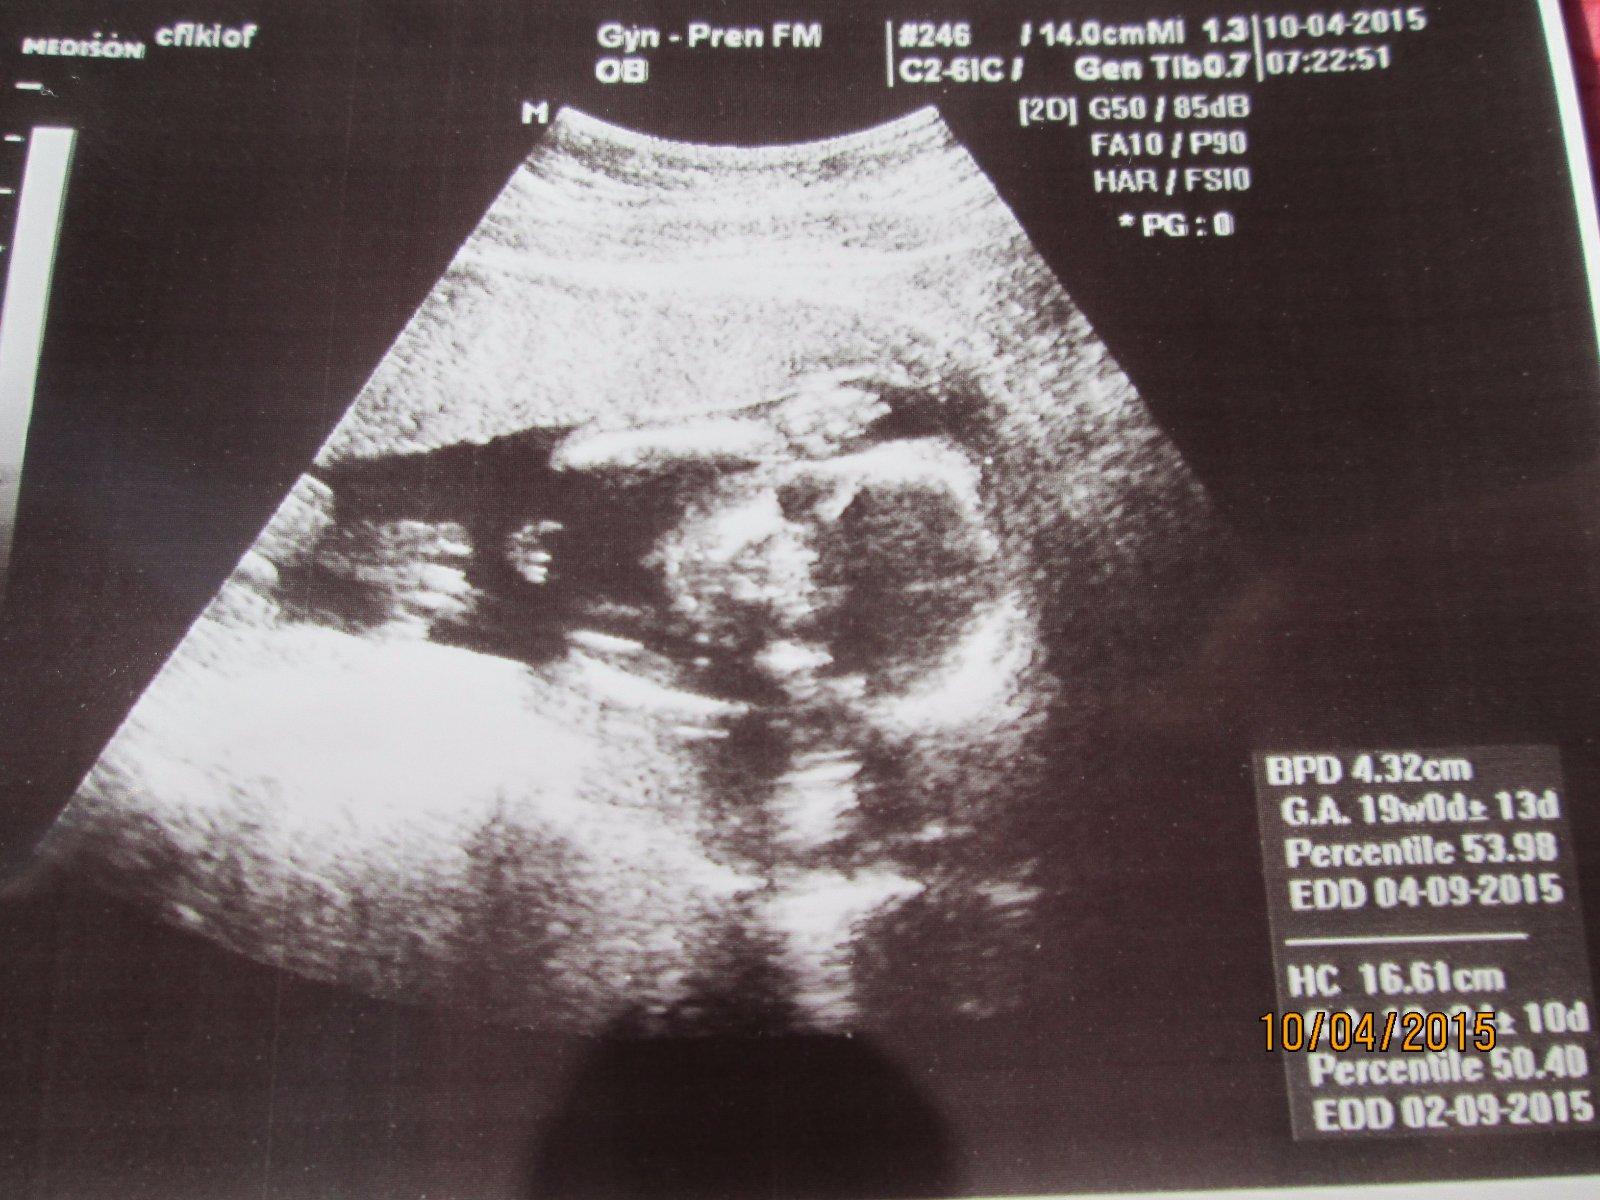

Pomozte mi Prosím odhalit pohlaví miminka

,jsem 17 tt a doktor mi zatím odmítá něco říct.Rekl mi jen že mi pohlaví vyfotí ať prý mam doma na co přemýšlet..